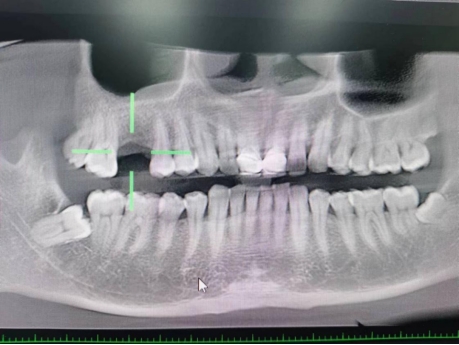

武先生术后检查图

据了解,53岁的武先生,因右上后牙缺失多年,缺失的牙齿给他造成了不小的烦恼,影响到了正常咀嚼功能。在了解到公司口腔科能开展种植牙手术以后,武先生前来咨询,经过仔细全面的口腔检查和CT检查、检验等检查,武先生符合种植牙条件,决定实施右上后牙区种植牙的修复方案。本次手术由陈河林博士主刀,黄魁副主任做助手,在口腔中心成功完成该院首例种植牙手术,手术历时约30分钟,术中微创操作,患者全程无痛,术后无不良反应,整个诊疗过程舒适、安全、精准,经术后CT检查种植体位置精确。